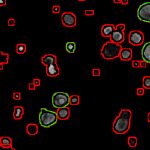

Epilessia e malattie della retina, scoperta molecola che apre la strada a trattamenti più efficaci.